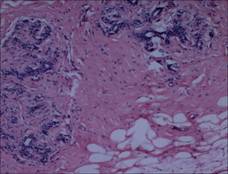

[設(shè)備圖片&實(shí)拍顯微圖片]

實(shí)拍示范圖片

實(shí)拍設(shè)備圖片(MC50+奧林巴斯BX43)